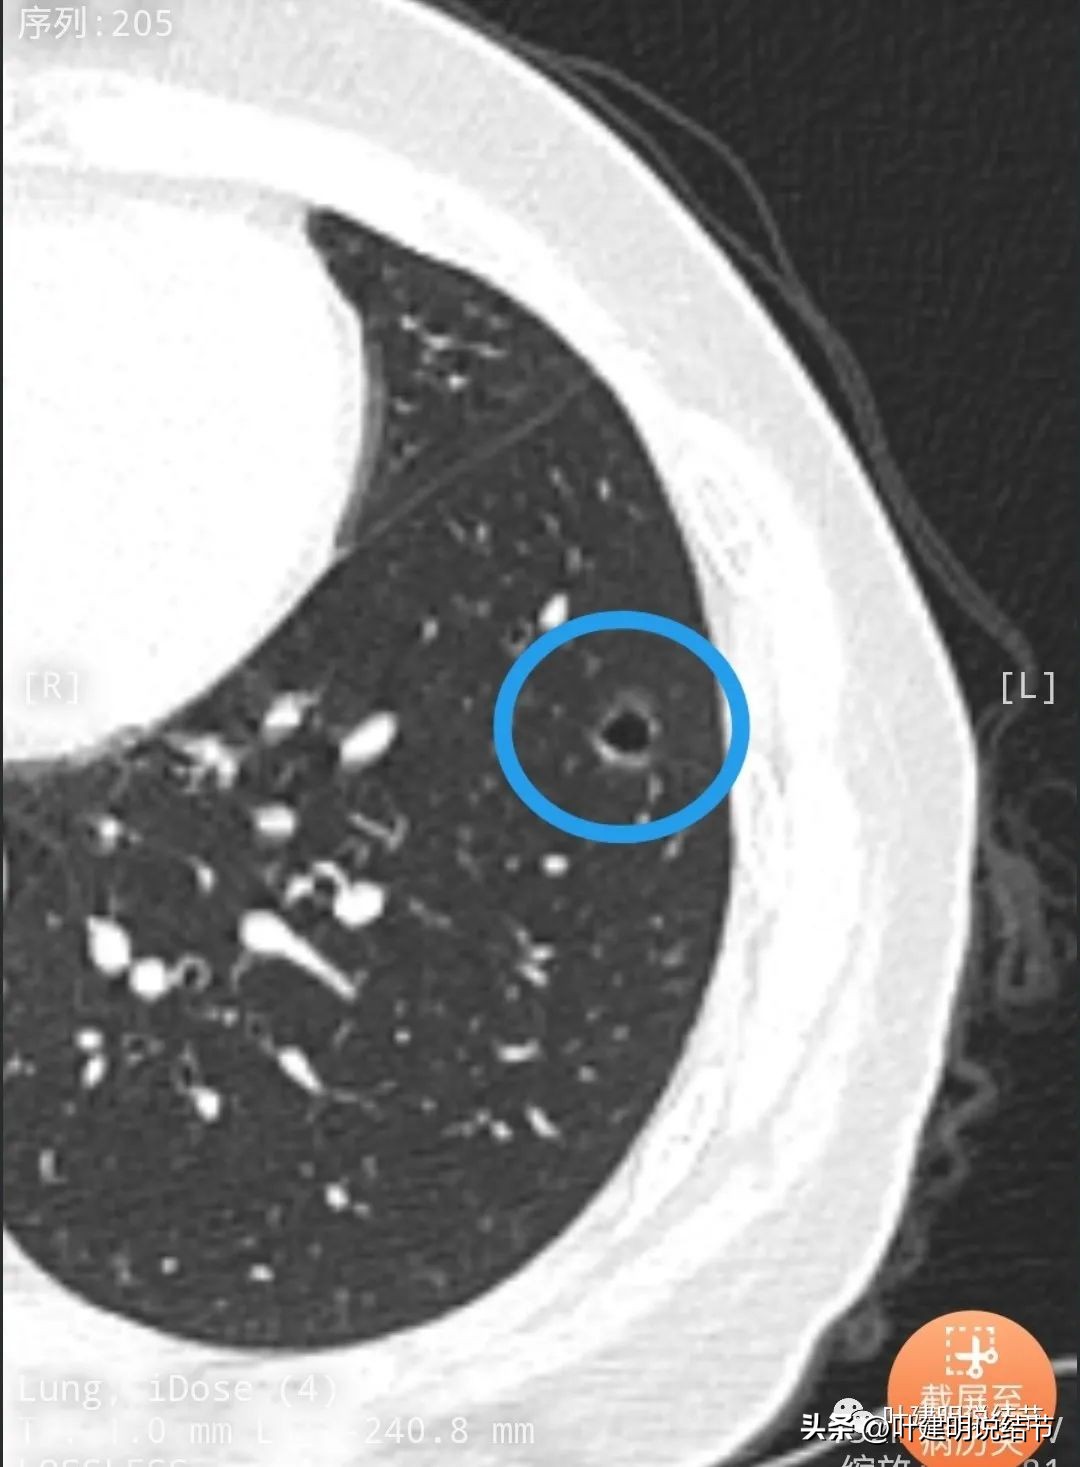

病灶中间有空腔。

囊壁较薄,但不均匀,有的地方还是显略厚了点的。

似乎见微小血管走向病灶。

微小血管征确实有。